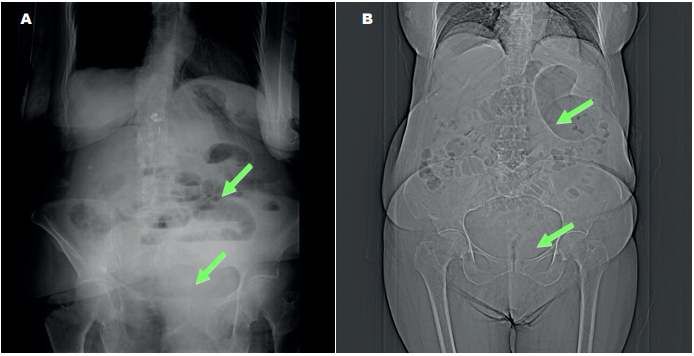

Dada su baja incidencia, la hernia obturatriz puede representar un reto diagnóstico para el radiólogo y el cirujano 20. La evaluación con radiografía convencional es inespecífica y en su forma de presentación como obstrucción intestinal muestra signos de distensión de asas y niveles hidroaéreos (Figura 4). Ocasionalmente se aprecia gas intraluminal (burbuja gaseosa) en las proximidades de la rama iliopúbica o del agujero obturador, siendo esta última muy sugestiva de hernia obturatriz 7,23.